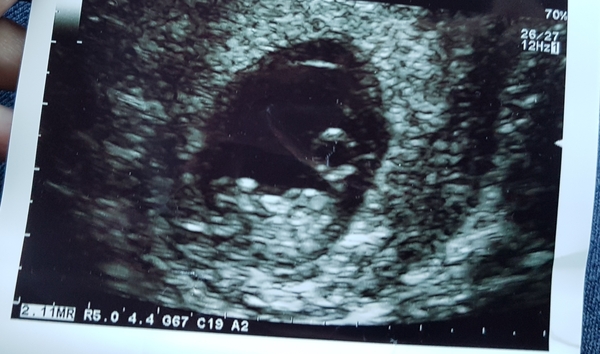

Thought I'd post on here properly for the 1st time..... DH n I went for a private scan today after me constantly worrying ( I had a mc last year) there is a good heartbeat which we got to see (I'm still amazed by it!) & we are measuring 7w 6d which puts my dates for 18th Sept bang on. Got my booking appointment in 9 hrs so kinda nervous n excited lol